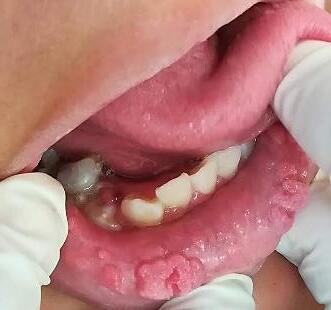

Presentación de caso clínico

Paciente femenino de 10 años de edadacudeaconsultaporlesionesmúltiples en la mucosa; de superficie rugosa, firme y

con un tiempo de evolución de tres años, refierequesuhermanamayortuvolesiones similares. (Fig. 7 y 8), se toma biopsia de una de las lesiones donde se observa presencia de paraqueratosis, hiperplasia epitelialconacantosisyanastomosisclavos epiteliales.

Fig.7 y 8

Hiperplasia epitelial multifocal, imagen clínica

Nota:Fototomadaporelautor

Algunosqueratinocitossuperficiales muestran un cambio coilocítico, también conocido como mitosoide (Fig 9). Después de entregar el diagnóstico de patología se recomendó imiquimod al 5 % para el resto de las lesiones las cuales fueron disminuyendopaulatinamente.